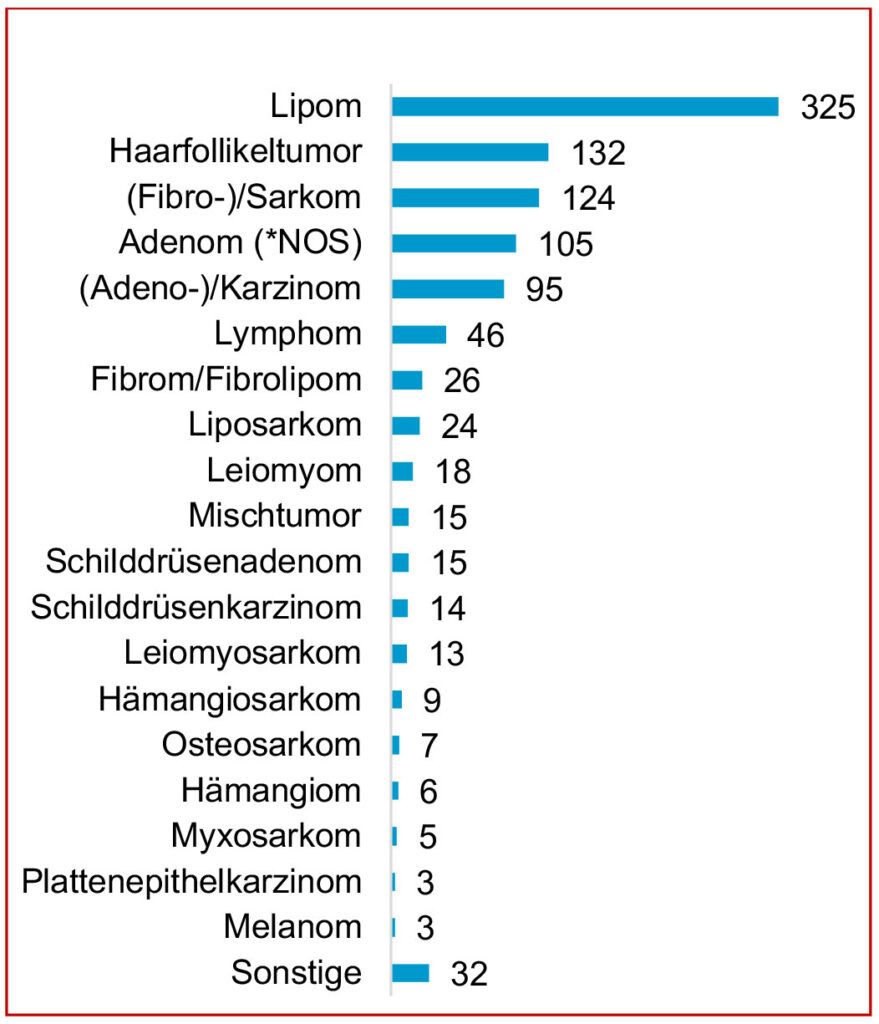

In dem Einsendungsgut lag das Lipom als häufigste Tumordiagnose beim Meerschweinchen an erster Stelle. An zweiter Stelle folgten die Haarfollikeltumoren. Zahlreiche weitere Tumordiagnosen konnten gestellt werden (Abb. 2). Da als Entnahmelokalisation die Haut und Unterhaut dominierten, ist es nicht verwunderlich, dass besonders die Fettgewebstumoren und die Haarfollikeltumoren als Diagnosen an erster Stelle standen.

Abb. 2: Tumordiagnosen beim Meerschweinchen im Einsendungsgut von Laboklin (2013–2020) *NOS: not otherwise specified.

Bildquelle: Laboklin